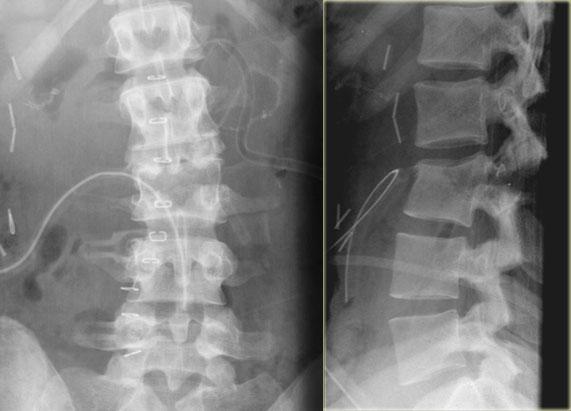

Hình ảnh bên trái của một nam giới 31 tuổi.

Anh ta đang làm việc trên mái nhà, ngã từ độ cao khoảng 5 mét và tiếp đất bằng hai chân.

Anh ta than phiền đau ở chi dưới bên trái và vùng thắt lưng.

Trước tiên hãy quan sát các hình ảnh, sau đó tiếp tục đọc.

Trên phim X-quang cho thấy tổn thương tăng gấp khúc của L1 với sự tổn thương cột trước và có thể tổn thương cột giữa.

Các tái tạo mặt phẳng đứng dọc trên CT cho thấy phần sau thân đốt sống có chiều cao bình thường, nhưng có một phần tổn thương ở phía sau thân đốt sống.

Hiện vẫn còn tranh luận về cách điều trị cho những bệnh nhân này và liệu MRI có vai trò gì trong những trường hợp này hay không.

Nếu đánh giá theo hướng tích cực, có thể gọi đây là tổn thương hai cột, đòi hỏi phải phẫu thuật cố định.

Nếu đánh giá theo hướng thận trọng, có thể gọi đây là tổn thương chỉ ảnh hưởng nhẹ đến cột giữa.